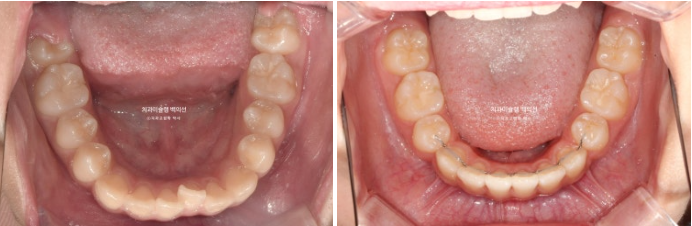

25.09

중심선은 잘 맞으며 앞니 교합은 적절합니다.

어금니 교합은 1급이고 좋습니다.

25.10~25.09

그 사이 두번째 큰어금니까지 모두 나와 잘 배열되었습니다.

총 치료기간은 1년 11개월, 중간에 쉰기간을 빼면 실제로 1년 9개월정도 됩니다.